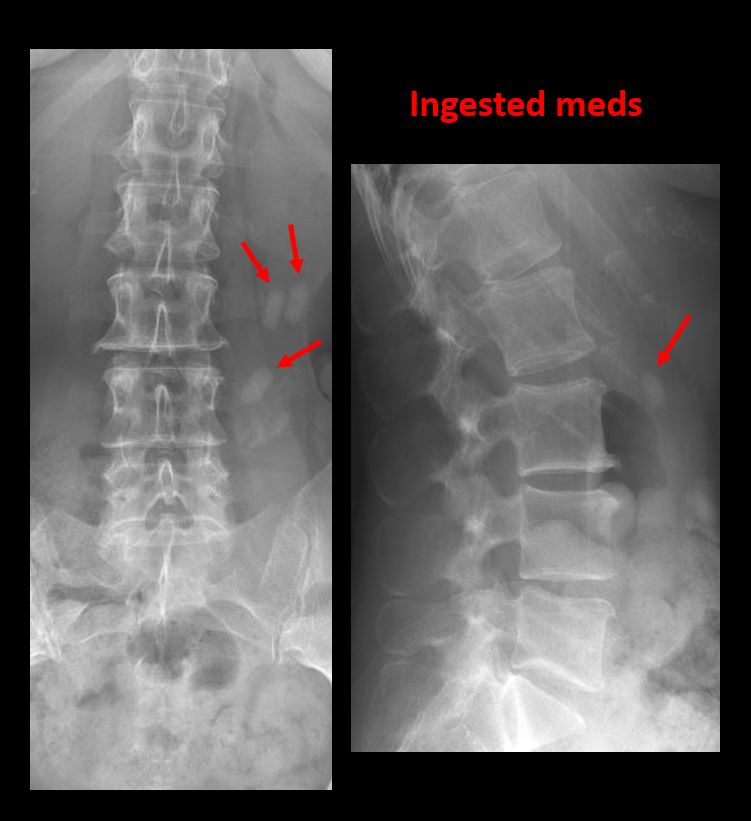

21 yo male with low back pain after trauma.Exam

There is an acute compression fracture of L4 with mild retropulsion of the posterior superior vertebral body into the spinal canal.

Direct communication with the ED physician at the time of dictation regarding the acute compression fracture of L4 and mild retropulsion into the spinal canal. Cross sectional imaging is recommended.

Urgent (Action Necessary in a few hours)